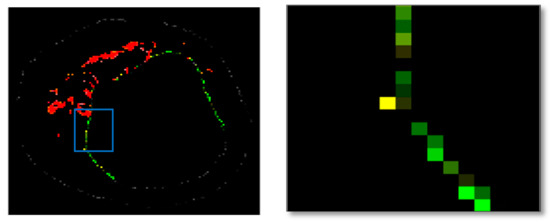

The result of the clustering algorithms will be strongly affected by the presence of outliers that do not belong to any of the clusters [28]. The purpose of outlier detection is to find small groups of pixels that are not similar to the rest of the pixels belonging to the same cluster [72]. Figure 5 illustrates the outliers with dark green, light green, etc., in an NC image. The zoomed area (b) is indicated by the blue box in the original image (a).

Figure 5.

Outliers in an NC image: (a) original image, and (b) zoomed area.

To provide more reliable results, outliers should be removed from the generated clusters. NC and DC images play an important role in TCFA detection; therefore, their outliers are removed for modifying the training set. First, the Euclidian distance between pixels belonging to the NC and its centre are calculated. Then, for each pixel in the NC image, if its distance is greater than the defined threshold value (TNC), then this pixel is an outlier, and its intensity should be replaced with zero. Based on the sub experiments, the value of TNC is changed, and intra-cluster distance (the distance between pixels and the centroid within a cluster) for the NC image are calculated. The value of TNC = 200 gave the best result for the minimum distance between pixels of the NC and its centre. In addition, outliers of DC image are removed in the similar way [45].